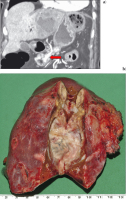

Abbildung 4: a) Der Leberabszeß mit Satellitenherden durchsetzt den linken Leberlappen (CT 8.8.2005). Die weiße Struktur entspricht dem über den Ductus Santorini in den Hauptpankreasgang eingelegten Stent. b) Präparat der linksseitigen Lobektomie vom 18.8.2005 mit eröffneten Leberabszessen.